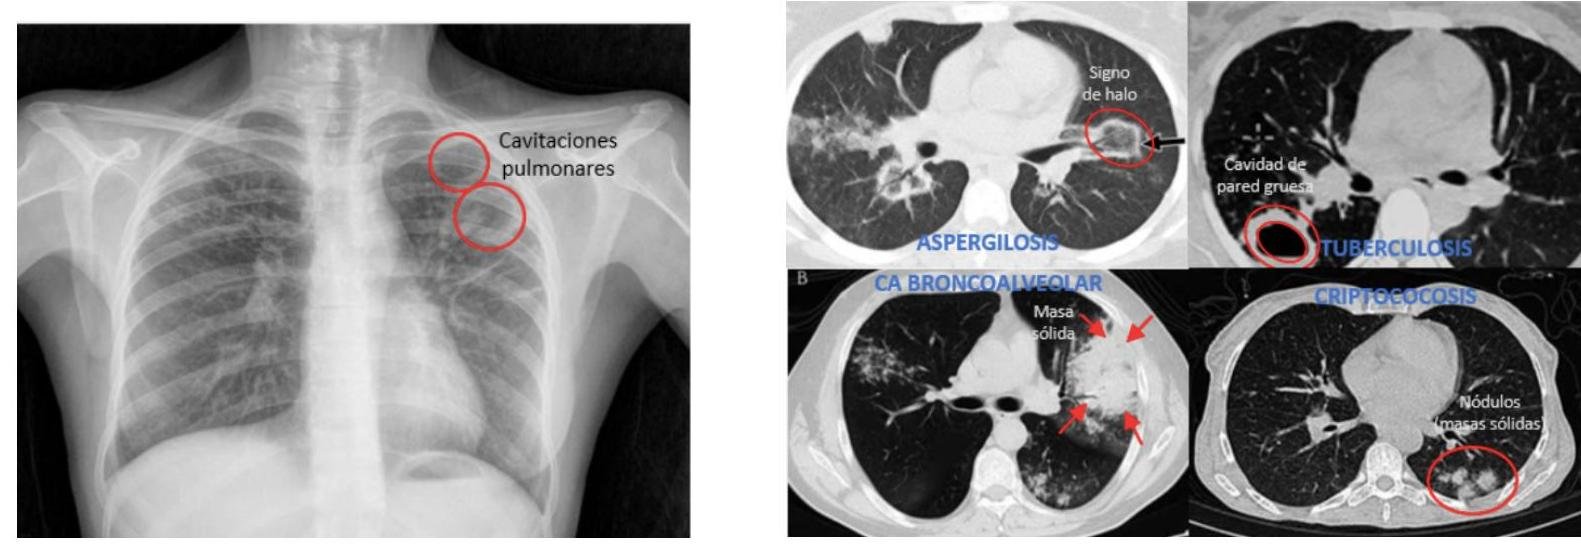

# TUBERCULOSIS PULMONAR ## DEFINICIÓN La tuberculosis pulmonar es una enfermedad causada por el complejo Mycobacterium tuberculosis. El grupo de Micobacterias que lo integran es *M. tuberculosis* (la más frecuente), *M. bovis*, *M. africanum*, *M. pinnipedii*, *M. caprae*, *M. microti* y *M. canetti*. La *Mycobacterium tuberculosis* es una bacteria aerobia, fina, no esporágena, bacilar y ácido-alcohol resistente. Se transmite por gotas respiratorias (tos, estornudo, respiración) y diseminación hematógena. ## CASOS DE TUBERCULOSIS | CASO NUEVO | Al establecer <b>DIAGNÓSTICO</b> por primera vez o si recibió <b>TRATAMIENTO</b> en menos de 30 días | | :--: | :--: | | CASO PREVIAMENTE TRATADO | Aquel que ha recibido al menos un <b>ESQUEMA DE ANTITUBERCULOSOS</b> por al menos 1 mes | | CASO PROBABLE | Tb Pulmonar: +2 semanas de tos con expectoración o hemoptisis (Si es niño: +2 semanas de tos con o sin expectoración, fiebre, diaforesis nocturna, dentición o baja de peso). Tb Meníngea: síndromes meníngeos con o sin antecedentes de contacto de caso de Tb pulmonar, con sospecha por cualquier auxiliar diagnóstico. (**NOTIFICACIÓN INMEDIATA**) Tuberculosis MDR: retratamiento primario o fármacos de segunda línea o contactos con casos conocidos de MDR. | | NO CONFIRMADO | Sintomatología, signos físicos, auxiliares de diagnóstico, respuesta terapéutica son sugestivos de TB, pero la baciloscopía, cultivo o métodos moleculares fueron negativos. | | CASO CONFIRMADO | Bacteriológicamente: desaparecen los signos clínicos y tiene baciloscopía negativa en los dos últimos meses de tratamiento o cultivo negativo al final del tratamiento. No bacteriológicamente: desaparecen signos clínicos y se observa mejora en los estudios de gabinete. Tb Resistente: al menos +5 cultivos negativos con intervalo de más de 60 días los últimos 12 meses de tratamiento. Si en este lapso se notifica +1 cultivo positivo sin ningún otro signo clínico puede considerarse curado si dicho cultivo va seguido de +3 cultivos consecutivos negativos con intervalo de 30 días. | | RESISTENCIA EXTENDIDA | Se identifica resistente in vitro a <b>ISONIACIDA</b> y <b>RIFAMPICINA</b> de manera simultánea, además resistencia a quinolonas y más de 1 de los de segunda línea inyectables (amikacina, kanamicina y capreomicina). | # TUBERCULOSIS EXTRAPULMONAR Diseminación hematógena, linfática o ingesta de bacilos de un foco pulmonar. - Ganglios linfáticos: principalmente cervicales, ocasionalmente axilares, claviculares: Linfadenopatías levemente dolorosas. | Tuberculosis renal |Hematuria, piuria ("estéril"), tuberculomas | | :--: | :-- | | Tracto Genital Femenino |Salpingitis e infertilidad | | Hueso |Osteomielitis, Mal de Pott | | Meninges |Meningitis tuberculosa, cefalea, focalización. La manifestación más grave extrapulmonar. | | Abdominal |Intestinal o peritoneal; diarrea, dolor abdominal. | | Ganglios |Cuando el ganglio cervical se rompe - Escrofula |   # EPIDEMIOLOGÍA - Es la enfermedad infecciosa humana más importante que existe a pesar de los esfuerzos para su control. - Se estima que 1 / 3 de la población está infectada por el bacilo de la tuberculosis. - LOS CASOS DE TUBERCULOSIS MENÍNGEA SON DE **NOTIFICACIÓN INMEDIATA** (24 horas). - La Tb Pulmonar es de **NOTIFICACIÓN SEMANAL Y MENSUAL**. ## FACTORES DE RIESGO Compromiso inmunológico: VIH, Neoplasias, Insuficiencia Renal o Hepática (en tratamiento con inmunosupresores), DM y Tabaquismo. ## FACTORES PARA TB RESISTENTE A TRATAMIENTO Y CRONICIDAD - Exposición a un caso de Tb MDR (multidrogorresistente) - Fracaso del tratamiento primario - Baciloscopía positiva al segundo o tercer mes de tratamiento - Recaída y regreso después de incumplimiento terapéutico - Exposición en instituciones con brotes de Tb MDR - Residir en zonas de alta prevalencia de TB MDR - Antecedente de uso de fármacos antituberculosis de calidad deficiente - Algunos casos de VIH ## CLÍNICA ## ASINTOMÁTICA La tuberculosis pulmonar puede ser asintomática en estadios tempranos, pero los síntomas (sistémicos o respiratorios) se desarrollan pronto. ## SINTOMÁTICA ## SISTÉMICOS - Ataque al estado general - Pérdida de peso - Fiebre - Sudores nocturnos ## RESPIRATORIOS ## Tos (síntoma más común) - Inicialmente seca y no productiva - Se convierte en productiva y con hemoptisis en algunos casos. ## Disnea - Es característica tardía - Ocurre cuando una cantidad de pulmón está destruido o existe derrame pleural. ## DIAGNÓSTICO ## TUBERCULOSIS LATENTE ## PRUEBA DE TUBERCULINA 1. Inmunidad específica por Linfocitos T. 2. PPD: **PURIFIED PROTEIN DERIVATIVE** (contiene proteínas comunes a **M. TUBERCULOSIS**). 3. Inyección intradérmica cara ventral antebrazo. 4. Se espera induración a las 47-72 horas (Reacción Mantoux). >5 mm **POSITIVA SI** - Contacto Tb activo - Coinfección VIH - Inmunocompromiso - Corticoesteroides - Trasplante de órganos - Cambios fibrosos en Rx - Hallazgos Clínicos Tb >>10 mm **POSITIVA SI** No reúne los criterios anteriores. # TUBERCULOSIS ACTIVA ## GOLD STANDARD: CULTIVO MEDIO DE CULTIVO: **LOWENSTEIN - JENSEN** (también se usa Ogawa). - Necesario para identificar las cepas aisladas. - La desventaja es la lenta capacidad de división de **M. TUBERCULOSIS**. - Resultado en al menos 4 a 6 semanas y costo elevado. ## Indicaciones: - Identificar la cepa. - Baciloscopía negativa y alta sospecha clínica. - Diagnóstico y seguimiento de previamente tratados. - Pacientes nuevos en tratamiento, con baciloscopía persistente positiva en segundo mes de tratamiento. - Pacientes VIH positivos en circunstancias especiales. - Tratamiento Estrictamente Supervisado (**TAES**). - Sospecha en niños. - Seguimiento bimensual en **MDR**. # BACILOSCOPÍA - El **BACILO DE ROBERT KOCH** (*Mycobacterium tuberculosis*) es la causa principal de la enfermedad. - Es una bacteria que no se visualiza bien con la tinción de Gram. - Se tiñe mejor con la tinción de **ZIEHL NEELSEN** (que usa alcohol ácido). - Debido a esto, se le reconoce como un **BAAR** (**BACILO ÁCIDO ALCOHOL RESISTENTE**).  Técnica de **ZIEHL NEELSEN** (Tinción para **BAAR** - Bacterias **ÁCIDO ALCOHOL RESISTENTE**) - Indicada en toda persona con tos o hemoptisis durante 2 o más semanas. - Se realiza un estudio seriado de **TOMA DE TRES MUESTRAS DE ESPUTO**. - Todo paciente nuevo, nunca antes tratado, y mensualmente en casos de vigilancia, recaídas y al término. - La toma y manipulación de la muestra influye en la sensibilidad de la prueba. - Tomarla antes de iniciar el tratamiento en espacios abiertos o bien ventilados. - Se toman en dos días consecutivos y enviadas a laboratorio lo más rápido posible, manteniéndola refrigerada. ## RADIOGRAFÍA DE TÓRAX - Técnica simple y MUY SENSIBLE para el diagnóstico de TB pulmonar. - Es completamente inespecífica ya que no hay signos patognomónicos por muy sugestivos que parezcan. ## **HALLAZGO CARACTERÍSTICO** - **INFILTRADO CAVITARIO EN LÓBULO SUPERIOR**. - Puede haber derrames pleurales, generalmente de un solo lado. - VIH + Tb Pulmonar: Infiltrados en el lóbulo inferior con o sin cavitaciones.  - Tuberculosis miliar: múltiples y finas densidades nodulares distribuidas en ambos pulmones (representan infiltrado hematológico o linfático). # PRUEBAS DE FARMACOSUSCEPTIBILIDAD - Se elabora un cronograma farmacológico e historial bacteriológico para reconocer posibles resistencias. - Se realiza simultáneamente al cultivo. - Esperar resultados antes de iniciar tratamiento. ## Indicaciones: - Pacientes con fracaso, recaída o abandono en tratamientos previos. - Contactos de **TB - MDR**. - Casos nuevos cuya baciloscopía persiste positiva al segundo mes de tratamiento. **POLIRRESISTENCIA**: aquellos casos en que las cepas infectantes de **M. TUBERCULOSIS** son resistentes in vitro a más de 1 medicamento de primera línea, excepto a la isoniacida y rifampicina simultáneamente. # TRATAMIENTO ## **PRIMERA ELECCIÓN**: TRATAMIENTO PRIMARIO ACORTADO. - **2 PPD positivas** son suficientes para iniciar Antifímicos. - El bacilo es de crecimiento lento, por lo tanto, difícil de erradicar. - Son indispensables los tratamientos prolongados. Medicamentos **ANTIFÍMICOS DE PRIMERA LÍNEA**: - Isoniacida - Rifampicina - Pirazinamida - Etambutol - Estreptomicina* ## **FASE INTENSIVA** - 4 fármacos (INH+RIF+PZA+EMB) $\rightarrow$ 2 meses ( 60 dosis) ($\mathbf{x 10}$ semanas) **DOTBAL FASE INTENSIVA** (10 SEMANAS O 2 MESES) Isoniacida + Rifampicina + Pirazinamida + Etambutol ## **FASE DE MANTENIMIENTO** - 2 fármacos (INH + RIF) $\rightarrow$ 4 meses (45 dosis) ($\mathbf{x 15}$ semanas) **DOTBAL S FASE DE SOSTÉN** (15 SEMANAS O 4 MESES) Isoniacida + Rifampicina ## **MADRE LACTANDO** Todos los antifímicos de primera línea son compatibles con lactancia. Madres con TB: - se debe extraer la leche de la madre y otro familiar debe dárselo. - El niño puede ser alimentado con seno directo si la madre cuenta con **2 BACILOSCOPÍAS NEGATIVAS**. ## EFECTOS ADVERSOS | | | | | :--: | :--: | :--: | | ISONIACIDA | Neuropatía periférica (administrar con Vitamina B6) | Hepatotoxicidad, especialmente si hay antecedente de hepatopatía. | | RIFAMPICINA | Orina, heces y sudor de color naranja. Inhibe anticonceptivos orales. | | | PIRAZINAMIDA | Hiperuricemia, Gota, Artralgias. | | | ETAMBUTOL | Neuritis Óptica, Discriminación Rojo-Verde. | | | ESTREPTOMICINA | Bloqueo neuromuscular, Lesión del VIII par, Nefrotóxico. No se debe usar en embarazo. | | ## **SEGUIMIENTO DE TRATAMIENTO** Se debe tener un seguimiento **MENSUAL CON BACILOSCOPÍA**. - Es favorable cuando resulta negativa al **SEGUNDO MES** y persista así hasta terminar las dosis, en caso contrario, se solicita un cultivo. El paciente puede regresar a trabajar después de **BAAR** y cultivo negativo. - Si al **SEGUNDO MES** sigue con baciloscopía positiva, se continúa el mismo esquema y se busca resistencia (no se cambia a fase de mantenimiento). - Si tiene una baciloscopía negativa que positiviza - **ENVÍO A SEGUNDO NIVEL** por probable falla terapéutica. Si se abandona o recae durante el tratamiento primario acortado, se sugiere tratamiento con 5 fármacos de primera línea durante 8 meses. (**RETRATAMIENTO PRIMARIO**) Si se fracasa, debe ser revisado por el **COEFAR** (**COMITÉ DE FARMACORESISTENCIA**) para determinar el esquema de segunda línea, pudiendo usar retratamiento estandarizado por 24 meses. # TRATAMIENTO EN DIFERENTES CASOS DE TB | | TB PRIMERA VEZ (6 meses) | RETRATAMIENTO PRIMARIO (8 meses) | ESTANDARIZADO SEGUNDA LÍNEA (24 meses) | FRACASO AL RETRATAMIENTO ESTANDARIZADO | | :--: | :--: | :--: | :--: | :--: | | | 2 meses de: - Isoniacida - Rifampicina - Pirazinamida - Etambutol | 2 meses de: - Isoniacida - Rifampicina - Pirazinamida - Etambutol + Estreptomicina | 6 meses de: a) Kanamicina b) Amikacina c) Capreomicina + - Levofloxacino - Protionamida - Cicloserina - Pirazinamida - Etambutol Toma: Diario | Individualizado y revisado por **COEFAR** | | | Toma: Diario | | | | | | | 1 mes de: - Isoniacida - Rifampicina - Pirazinamida - Etambutol | | | | | 4 meses de: - Isoniacida - Rifampicina Tb Ósea: 7 meses Tb Meníngea: 10 meses Toma: L - Mi - V (bajo supervisión) | 5 meses de: - Isoniacida - Rifampicina - Etambutol Toma: L - Mi - V (bajo supervisión) | 18 meses de: - Levofloxacino - Protionamida - Cicloserina - Pirazinamida - Etambutol Toma: Diario | | # **PROFILAXIS DE CONTACTOS** Entre un 30-40 % de los contactos cercanos de un paciente con Tuberculosis Pulmonar desarrollan una **TUBERCULOSIS LATENTE**. - El mayor riesgo de contagio a contactos es cuando el enfermo tiene **CAVERNAS**. La búsqueda de casos debe realizarse de manera sistemática para casos de tuberculosis activa o infección latente en grupos conocidos que están en alto riesgo (**BÚSQUEDA ACTIVA**).  # **PREVENCIÓN** En países como **MÉXICO**, se recomienda la vacunación contra Tuberculosis a **TODOS LOS RECIÉN NACIDOS** o en el primer contacto con los servicios de salud **ANTES DEL AÑO DE EDAD**. ## **VACUNA BCG** - Produce inmunidad activa contra tuberculosis y disminuye la incidencia de la TB en el SNC. - Se elabora con bacilos de Mycobacterium bovis vivos atenuados (bacilo de Calmette y **GUÉRIN**=BCG). - Cada dosis de 0.1 ml contiene como mínimo 200.000 UFC. - Todos los vacunados pueden ser revacunados al ingresar a la primaria por indicaciones epidemiológicas. - Los pacientes que tienen **TUBERCULOSIS LATENTE** pueden beneficiarse de tratamiento preventivo. Protección (formas graves): - **TB MENÍNGEA** - **TB MILIAR** **CONTRAINDICACIONES**: - RN con menos de 2.000 g. - Lesiones cutáneas en sitio de aplicación. - Inmunodeprimidos por enfermedad o tratamiento. - Fiebre >38,5 °C. - Transfusiones o inmunoglobulina en los últimos 3 meses. - SIDA. - Embarazo.